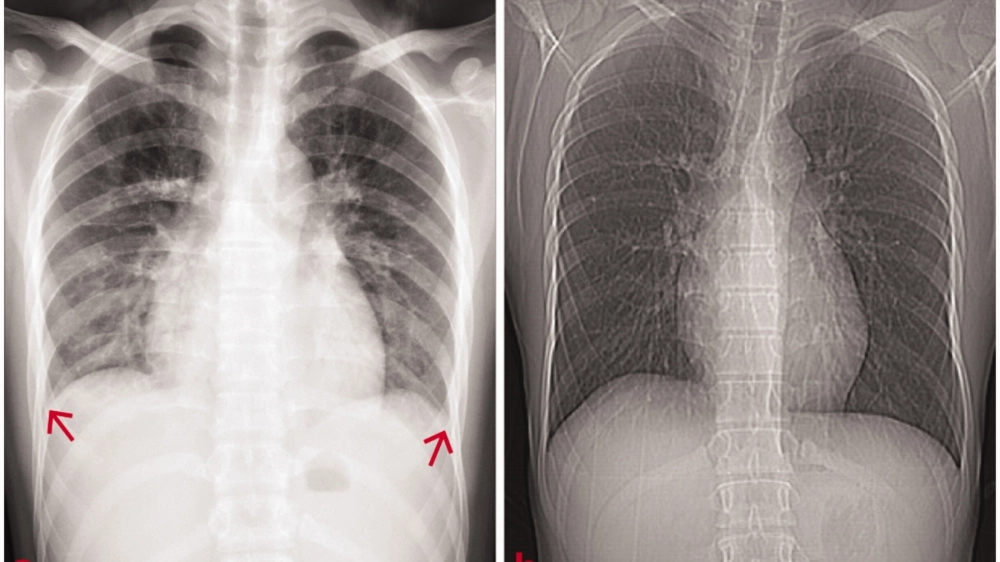

• Phù là triệu chứng rất điển hình, thường xuất hiện ở mặt (mí mắt) vào buổi sáng, sau đó có thể phù toàn thân, kèm theo tăng huyết áp.

Biểu hiện của hội chứng thận hư